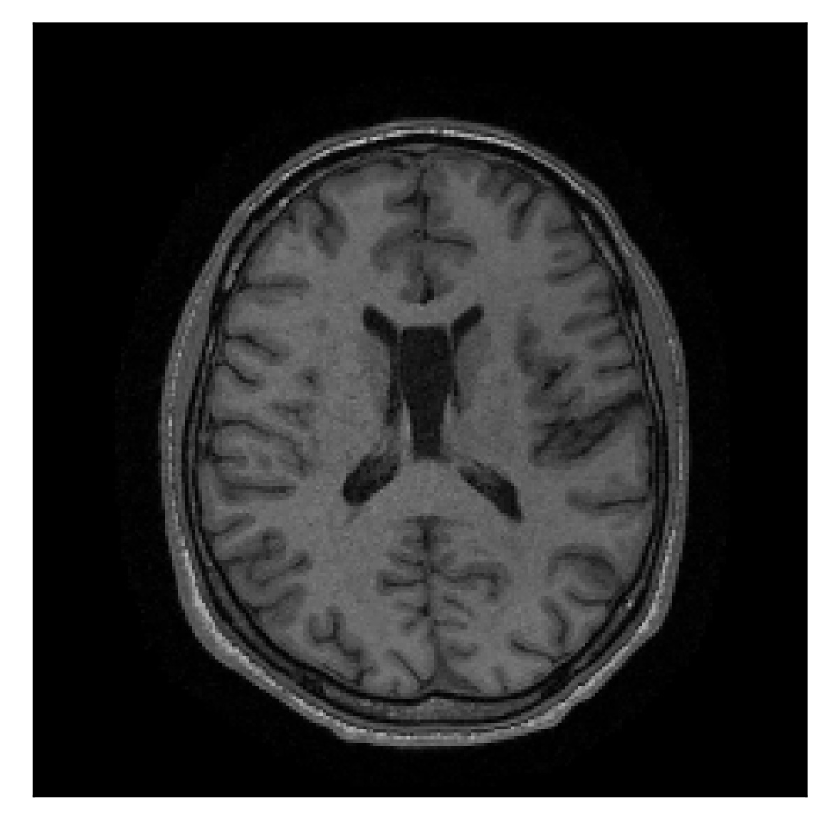

3.3 Experiment 3: scanner reconstruction vs processed raw k-space data as input for retrospective motion correction

With the in-vivo studies presented in this section, we investigate a question related to the nature of the input data (equation 6) required by the algorithm. Due to the formulation of the problem directly in -space (by means of the NUFFT), the method assumes coil-resolved data. One must then assess whether the scanner reconstruction (available in the DICOM format) is suitable for this purpose, since many different reconstruction methods are available depending on the acquisition protocol. In particular, the default reconstruction method for linear-filling patterns in -space employs the SENSE framework [Pruessmann et al., 1999], while compressed-sensing reconstruction (via the wavelet transform) is used for randomized acquisitions [Lustig et al., 2007]. Note that our experimentation suggests that without the phase map of the scanner reconstruction our motion correction scheme does not perform adequately. Therefore, with “scanner reconstruction”, we will always refer to the complex-valued scanner reconstruction (comprising both the respective amplitude and phase).

In the first experiment, we asked volunteer 3 to change position once during the prospectively-corrupted acquisition. We consider a corrupted T2-weighted contrast and a reference T1-weighted contrast (see Table 1). One important aspect of this experiment is related to the acquisition protocol of the T2-weighted contrast, based on a linear-filling pattern in -space. The corrupted data used as input for the proposed motion-correction algorithm is obtained by exporting the reconstructed volume directly from the scanner, followed by a simple Fourier transform. Note that this 3D image has been obtained by a SENSE reconstruction.

| Section 3.3, Figure 12 | Sagittal | 22.26 | 27.54 | 0.6963 | 0.8409 |

| Coronal | 23.46 | 31.65 | 0.7321 | 0.8370 | |

| Axial | 24.55 | 32.33 | 0.7895 | 0.8144 | |

The motion-corrected full-volume scans were analyzed by a neuroradiologist with 16 years of experience. These were generally deemed of good radiological quality. The motion-related artifacts have been completely removed, and the results are quite close to the ground truth. In Table 3, we organized a more detailed qualitative analysis of the 3D results, geared toward a radiological assessment of the corrected scans.

| Section 3.3, Figure 12 | T2 | Completely corrected | No blurring | No additional artifacts | |

4.3 Experiment 3: scanner reconstruction vs raw k-space data

The results of the two experiments described in Section 3.3 are depicted in Figures 12 and 14. The main difference between the two experiments is related to the input data for the proposed motion-correction algorithm.

In the first experiment, the corrupted contrast has been acquired with a protocol based on a linear filling pattern in -space. Note that, in this particular case, the scanner reconstruction implements the SENSE method. We then extracted the DICOM of both amplitude and phase produced by the scanner, and used it as input data (after a Fourier transform) for the algorithm. The proposed scheme is able to successfully remove the motion artifacts in Figure 12.

The method here presented is limited to rigid motion. Indeed, some decrease in correction quality is noticeable in Figure 12 in the neck region (which is not supposed to behave rigidly). However, our technique may be extended to non-rigid motion and, hence, different body regions other than the brain [see, for example, Huttinga et al., 2020]. A major challenge for such extension is a computationally effective parameterization of the motion effects, and the resulting ill-posedness of the inverse problem. Note that a significant computational advantage of rigid motion over non-rigid motion is related to the direct implementation of the rigid motion in -space, via equation (3), which results in a data model that requires a single NUFFT evaluation, regardless of the number of time samples considered. Other interesting extensions of the method are related to the integration of specialized motion-resilient acquisition patterns, e.g. as described in Cordero-Grande et al. [2020].

Sagittal

Coronal

Axial

Axial detail